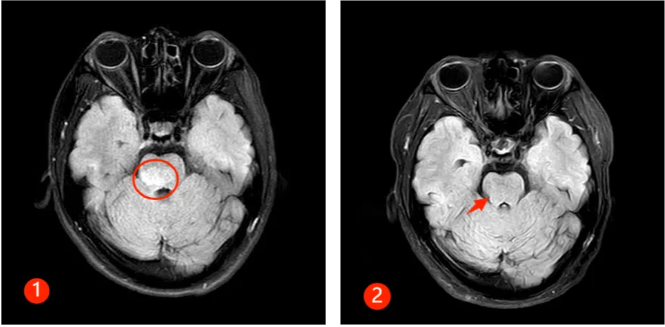

半年前,30来岁的谭先生突然出现颈肩部疼痛不适及肢体麻木,此后短短数天迅速出现四肢瘫痪及大小便失禁,生活不能自理。正值风华正茂的年纪,谭先生一时无法接受,心急如焚的父母带着吓坏了的谭先生来郑州大学第五附属医院就诊,入住神经内科二病区。入科时患者已四肢全瘫,紧急完善相关检查,发现患者脑干、颈髓、胸髓、腰髓广泛病变(见图①),随后完善腰穿及相关抗体检查,最终确诊为MOGAD。

经过及时的免疫治疗,患者病情逐渐好转,出院时患者已能下床行走,再次拾起对生活的信心,复查磁共振,患者脑干、颈髓、胸髓、腰髓的病变已明显好转(见下图②)。半年后随访,患者已恢复正常的生活,预后非常好。